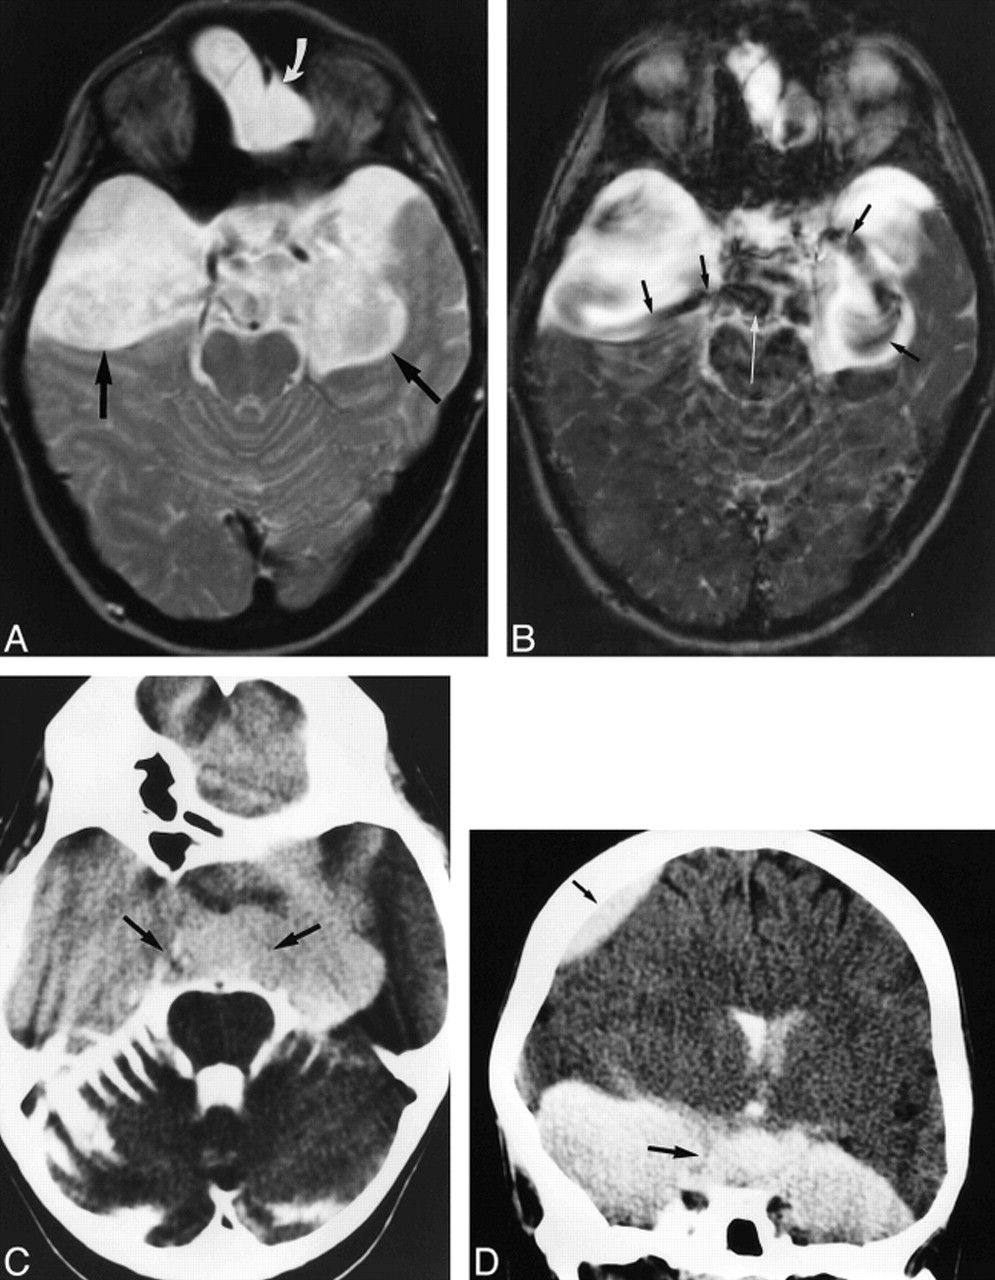

44-year-old man with left-sided tinnitus and hearing loss, paraesthesia, and respiratory distress.

A, T1-weighted transverse image (500/12/2) of the posterior fossa shows a paramedullary, space-occupying lesion with signal intensity similar to CSF, compressing the left ventrolateral portion of the medulla oblongata (arrow).

B, T2-weighted SE image (2000/80/1) of the same section as in A. Different compartments are not visible; the lesion has the same signal intensity as the surrounding CSF spaces, and margins of the cyst are not reliably detectable, making the diagnosis of an arachnoidal cyst highly probable.

C, Corresponding preoperative SSFP image (20/25/1) shows a circumscribed, hyperintense, premedullary lesion (large arrow), indicating stationary CSF of a noncommunicating arachnoid cyst in contrast to the significantly reduced signal of moving CSF in neighboring compartments (small arrows) and in the fourth ventricle (arrowhead). This finding strongly supports the decision for neurosurgical intervention.

D, SSFP image (20/25/1) after membranectomy shows signal attenuation in most parts of the formerly hyperintense cyst (arrow), indicating communication with neighboring CSF spaces. The patient experienced relief of his symptoms.

31-year-old woman after membranectomy of left temporal and right temporofrontal arachnoid cysts.

A, Transverse T2-weighted SE image (2000/80/1) shows slightly inhomogeneous, hyperintense temporal cysts (straight arrows). The frontal part of the large right-sided cyst is depicted (curved arrow).

B, Corresponding SSFP image (20/25/1) of the same section clearly shows a jet phenomenon with distinct signal reduction arising from the right prepontine and left chiasmatic cisterns, indicating communication between the cysts and cisterns (black arrows). Marked signal reduction results from moving CSF in the prepontine cistern (white arrow). The contents of the arachnoid cysts appear, with local flow attenuation, more inhomogeneous in the SSFP image (20/25/1) owing to higher sensitivity to turbulent flow.

C and D, Transverse (C) and coronal (D) CT cisternograms show homogeneous contrast enhancement within the basal cisterns and both the left temporal and right temporofrontal cysts. The regions of bilateral membranectomy are indicated by arrows. The coronal image also shows a frontal part of the right cyst (small arrow).